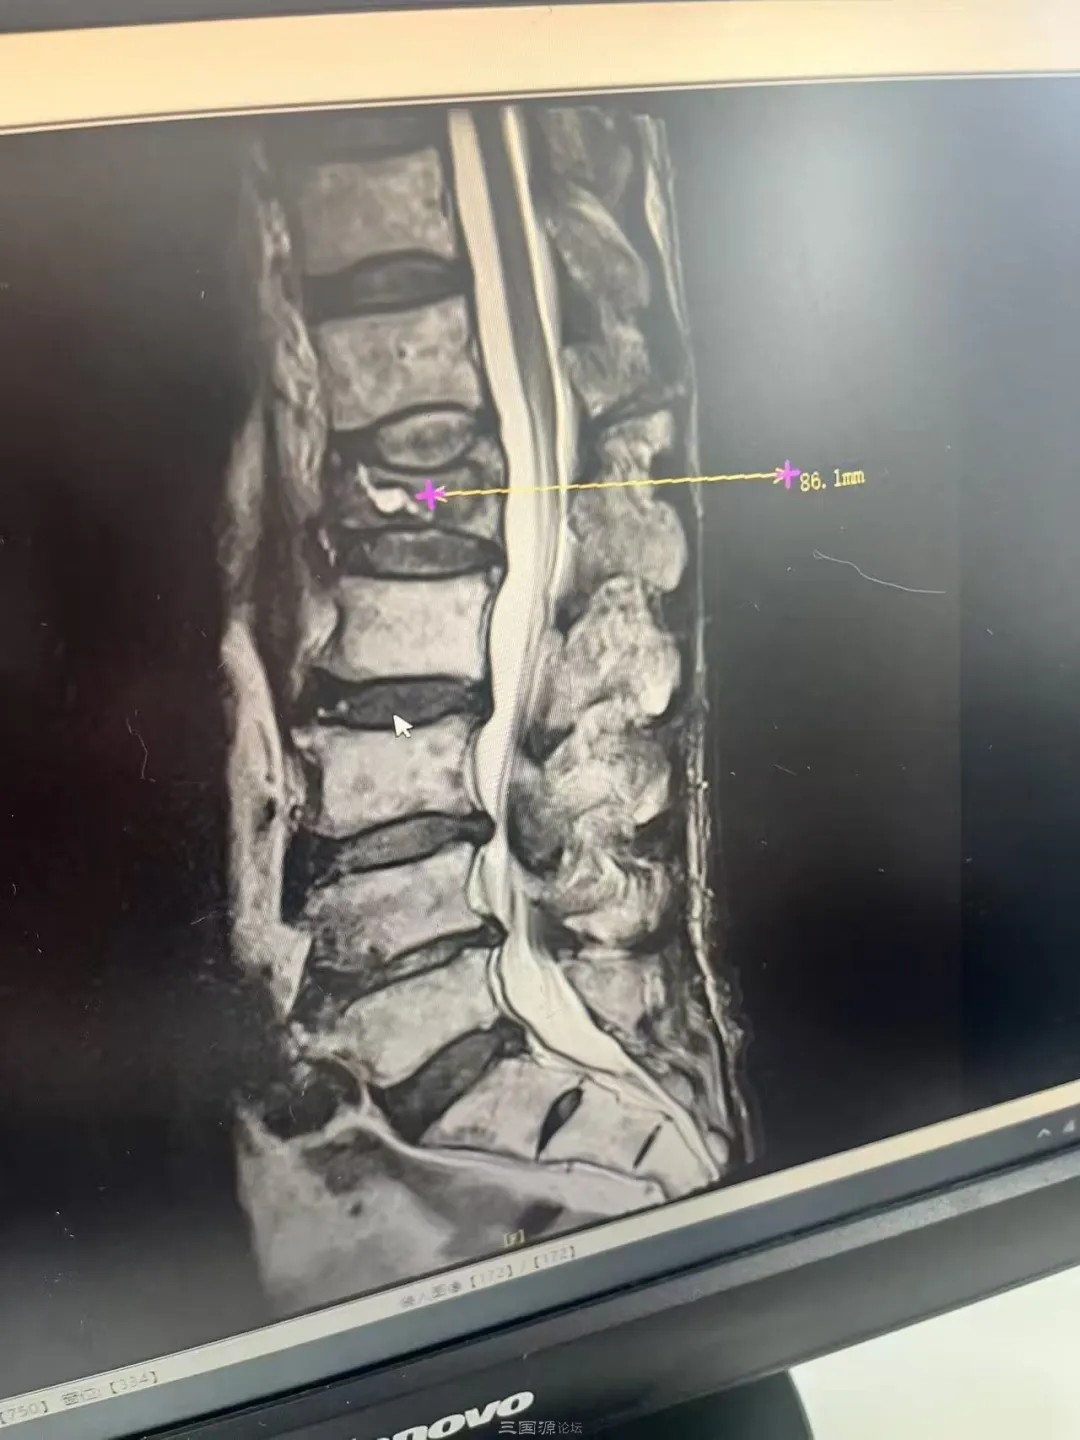

蓬安徐家镇两位70多岁的老人下地干活被摔伤,他们房前的一条马路被雨水冲垮,马路被冲垮导致他们家房子成了危房,请求相关部门帮帮老人为盼 2025年11月22日,群众再次实名反映:我叫蒋立明,男 ,现年73岁,我家住在蓬安县徐家镇书房梁村,家中现只有我和我的妻子两人,妻子也70多岁了,我今年73岁了,长期患有严重腰椎间盘突出骨质增生,坐骨神经痛、还有支气管炎、心脏病,我前不久下地干活的时候,不幸将我的腰椎骨跌断了。 我妻子有脑梗,鼻炎,腰椎间盘突出、骨质增生、心血管病,我的妻子又于2025年5月1日不幸左脚骨折,丧失了劳动能力,我们因为现在年事已高,加上疾病缠身,家庭经济陷入极端贫困的处境,我的两个女儿都出嫁了,大女儿莫得任何工作,无任何经济来源。二女儿在营山打工,工资微薄,她们养活她们自己都很困难。 两个老人因为为了治伤,到处借钱,导致债台高筑,目前生活非常困难。 屋漏偏逢连夜雨,近日,老位老人居住的房子前的一条马路,被雨水冲垮了,这条马路被冲垮,导致老人居住的房子的地基受到严重影响,导致房子的地坝多处开裂,房子几乎成了危房,两位受伤的老人住在房子里面每天都提心吊胆,十分害怕。 如今,两位70多岁的老人年老体弱,身体多病,丧失了劳动能力,生活非常困难。强烈请求相关部门能够给予两位70多岁的受伤的老人以最起码的帮扶为盼。谢谢尊敬的各位领导。 申请人:蓬安徐家镇书房梁村73岁老人蒋立明 声明:反映情况的网友发来的文字、图片、视频只代表网友的观点和意见,并不代表平台的观点和意见。 具体情况,请以相关部门公布的最终调查结论为准。